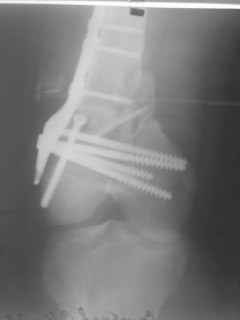

01.12.09г. оперировал больного с подобной травмой в ЦРБ на 4-е сутки после ДТП. Перелом открытый - рана находилась медиально чуть выше надколенника длиной примерно 3-4 см. До этого при поступлении было выполнено ПХО раны и скелетное вытяжение. На момент операции рана без признаков воспаления, состояние больного удовлетворительное.На первичных снимках перелом А3. На операции оказалось С3. Перелом фиксирован мыщелковой пластиной. Для репозиции понадобился медиальный доступ. Медиальный блок дополнен костно-губчатым аутотрансплантатом. На сегодняшний день раны заживают первично, швы еще не сняты, температура тела нормальная, отек бедра значительно уменьшился, имеется анемия средней степени, проводится ЛФК. Фото досылаю

|

Чем остеосинтез аппаратом в этом конкретном случае был бы предпочтительнее - и менее инвазивно, и пластику бы не надо было делать, и ось можно было бы лучше контролировать, включая послеоперационный период. А сейчас варусный коллапс градусов 15, и для исправления оси потребуется отдельная операция...

Снимки лучше бы делать на большем протяжении.